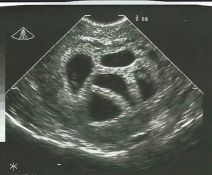

Zatrudnjela s petorkama, liječnici savjetovali smanjenje fetusa: 20 godina kasnije pokazala ovu fotku

uzv5.jpg